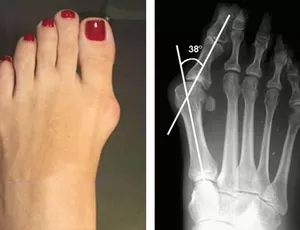

Um joanete, também conhecido como hálux valgo, é uma deformidade óssea que ocorre na articulação na base do dedão do pé. Essa condição é caracterizada por uma protuberância óssea que se forma na borda interna do pé, onde o dedão se encontra com o restante do pé.

Os sintomas de um joanete podem incluir dor, inchaço, vermelhidão e rigidez na articulação do dedão do pé. Esses sintomas podem piorar ao caminhar ou usar sapatos apertados. Em estágios mais avançados, o dedão do pé pode se desviar em direção aos outros dedos, causando deformidade adicional e dificultando a mobilidade.

Em casos mais graves, quando os sintomas são persistentes e impactam significativamente a qualidade de vida do paciente, ou quando a deformidade interfere na função do pé, a cirurgia pode ser considerada. Existem várias técnicas cirúrgicas disponíveis para corrigir um joanete, incluindo a remoção do tecido ósseo excessivo, realinhamento da articulação e correção da deformidade.